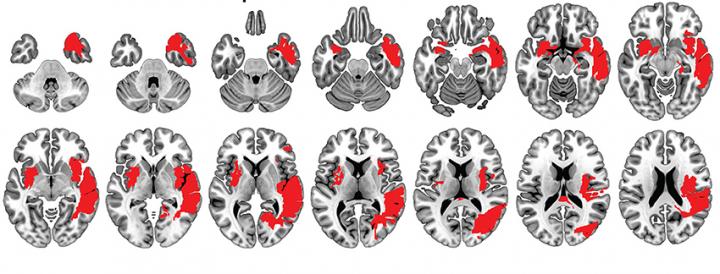

It turns out that this is often but not always the case. In a recent paper, a team of researchers from INCYT, based in Argentina, describes a woman who remains remarkably functional after enduring first a hemorrhagic and then an ischemic stroke. These events combined to create multiple lesions, which damaged many areas on both the right and left hemispheres of her brain. Normally such disturbances would be deeply harmful. For the woman in question here, a 44-year old known as CG, these events had only mild impacts.

The research team verified CG's resilience in multiple ways. First they assessed her sense of smell, taste and emotional recognition (the ability to interpret emotions in other people's facial expressions) in comparison to a control group of women without brain lesions. Despite a reduced sense of smell, CG performed within a normal range on almost every respect. Additional comparisons showed that CG exhibited no impairments of attention, memory, language or social cognition skills (such as inferring the meaning of others' emotions and thoughts).

Two members of the research team also visited CG at her home, which is a more true-to-life setting than a somewhat artificial research lab environment. As her mother and a long-time friend confirmed that CG's functioning was normal, CG herself was an exemplary host who was highly attuned to everyone's needs. This revealed high cognitive functioning, almost as though her lesions had never occurred at all. Indeed, the only impacts that endured over time were her compromised sense of smell as well as a loss of sensitivity in CG's right hand.

Other people with brain lesions have also shown surprising resilience -- for example, some people can maintain their language skills even after the left hemisphere of their brain is removed. In general these cases involve lesions to a single brain region. CG's case is unique because she endured multiple lesions extended across the brain and yet maintained strong functioning. One possible cause for this is that her brain "re-wired" itself to maintain its former level of functioning, which often occurs in similar cases. This process involves "plastic changes" in the brain.